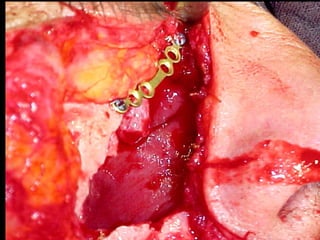

Trismus importante debido a que

El tumor ya rompió el hueso com-

Pacto de la cara interna de la

Mandíbula y empezó a tomar el

Músculo pterigoideo interno y

milohioideo.

Sierra de GigliSierra de Gigli

Luxación de hemimandíbula

Pieza quirúrgica

Plantilla flexible para dar forma previa al implante

Se respetó el cóndilo para anclar la prótesisSe respetó el cóndilo para anclar la prótesis

Límite tumoralLímite tumoral

Area de lisis ósea a nivel de la línea

Miliodes que contracturó los músculos

Milohioideo y pterigoideo interno

Dificultando la deglución y determinando

Trismus importante.

Pieza en proceso de examen por histopatología

Dr. Ismael Espejo Plascencia Patólogo

48 horas de post-operatorio